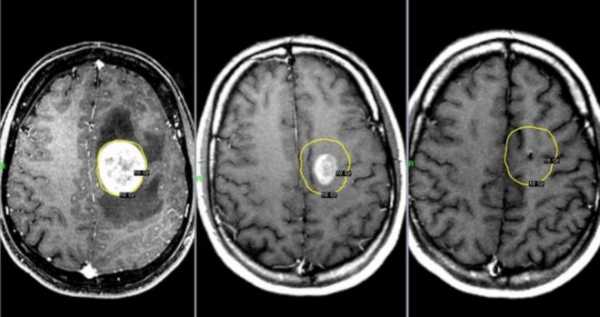

Ключевая роль в неврологической диагностике мозговых опухолей принадлежит рентгенографии, а также компьютерной и магнитно-резонансной томографиям. Эти методики применяют цифровую обработку результата рентгенологического обследования, что выявляет расположение и форму раковой опухоли.

Важнейшим инструментом диагностики опухоли головного мозга является компьютерная томография. Благодаря этому исследованию вы можете определить тип опухоли головного мозга, оценить ее состояние и угрозу инвагинации.

Несмотря на то, что компьютерная томография дает очень много информации о величине и расположении опухоли, что, в сочетании с другими факторами, позволяет определить ее тип, но для точного диагноза выполняется стереотаксическая биопсия с целью получения материала для оценки гистопатологии.